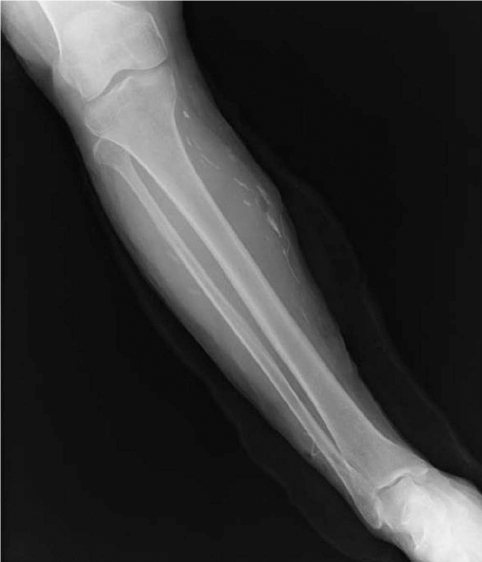

During the surgery, a small longitudinal incision was made on the upper portion of the elongated mass. A white-shiny, synovium-like piece of tissue popped out through the incision, and this was determined to be a sparganum that measured 18 cm in length and 0.5 cm in width, wriggling after removal from the patient. It was diminished to 13 cm in length and 12 mm in width after fixation in 10% formalin (Fig. 3). The calcified foci near the calf were also removed, and the pathologic examination revealed tubular tracts in the subcutaneous tissue (Fig. 4). These tracts possibly represented the pathway along which the larvae had passed. The tracks showed multiple, benign fibrocalcific nodular lesions with a few skeletal muscle fascicles, and the lesions were markedly degenerated (Fig. 5). The patient was a farmer, and she denied ingesting snake or frog meat, but she admitted drinking untreated mineral water from a local mountain. On the third postoperative day, the patient was discharged and followed up uneventfully.

In a patient with sparganosis, the characteristic host tissue reaction is an elongated tract-like cavity through which a larva has passed [16]. The sequential pathologic changes of sparganosis were reported as the followings; an inflammatory cell infiltration develops in the first week after the inoculation of the larvae into the soft tissue, tunnel-like structures appeared 2 weeks later, and a fibroblast proliferation appears about 4 weeks after that and this lasts as long as 6 months. If the larva migrates and then dies, the tunnels with inflammatory foci are replaced by granulation tissue [17]. In the present case, the tract was replaced by granulation tissue and calcium nodules were deposited on it. Hence, the tract of this case seems to have been formed at least years ago, supporting an old age of the present worm. However, the comparison of pathologic findings between the present case and other old sparganosis was not possible since the histological examinations of sparganosis were mostly done only on the nodule containing the larva, not the migration tract. For example, histological examination of a 19-year old sparganosis revealed suppurative, granulomatous dermatitis and panniculitis with spaces containing cross-sections of a cestode larval worm [10].